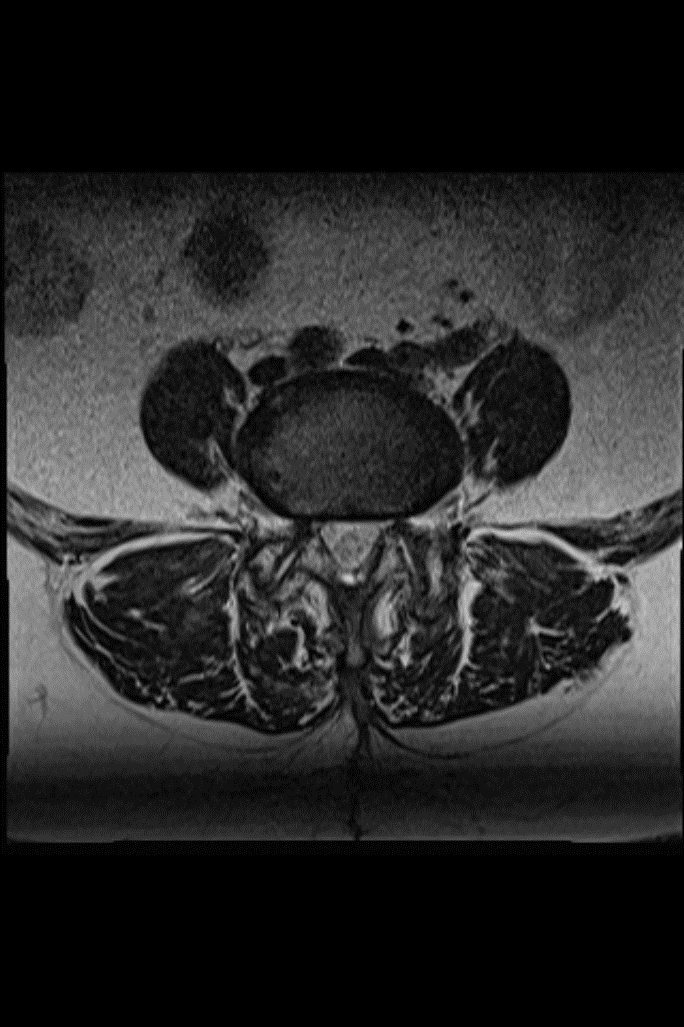

腰部脊柱管狭窄症(MRI)

頚椎症性脊髄症(MRI)